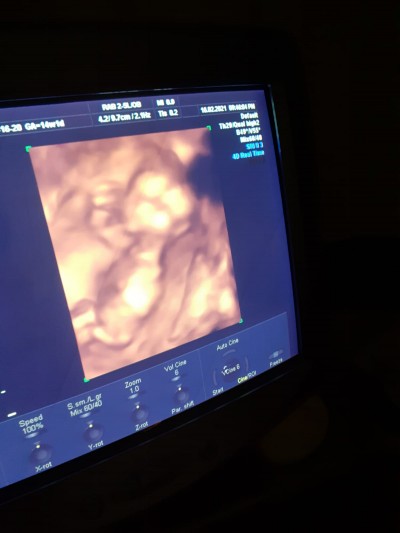

Bebeğim bacaklarını açmıyor bende çok merak ediyorum anlayanlar ultrasona bakıp tahminde bulabilir mi şimdiden çok teşekkür ederim